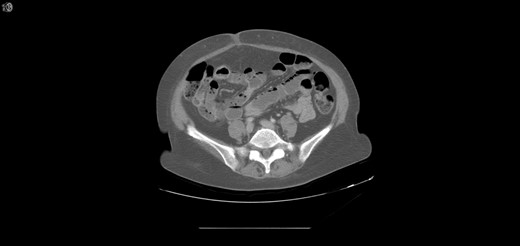

One year later, the patient was brought to the emergency department by her family for altered mental status. They reported 2 days of abnormal behavior and confusion culminating in an episode of bowel incontinence. The patient had difficulty following commands and was complaining of abdominal pain. Initial workup showed tachycardia, hypotension, leukocytosis and elevated creatinine which was treated per sepsis protocol. Her toxicology screen was positive for cocaine. Serum lactate was also elevated. CT brain without contrast showed no acute intracranial process. CT without contrast of the abdomen and pelvis, shown in Figs 3 and 4 , revealed dilated small bowel with gas in the bowel wall. Emergent damage control surgery was performed. There were no signs of gastrointestinal perforation but two segments of necrotic small bowel, 5 feet in total, were removed and the abdomen was sealed with Abthera. Two days later, her abdomen was re-explored and another 40 cm of non-viable small bowel was removed, leaving her with two small bowel anastomosis. Her abdomen was re-explored and closed after another 2 days. She was successfully weaned off the ventilator and continued to improve with supportive care. Final pathology examination revealed extensive necrosis with acute inflammation impacting the serosa at points in the small bowel.

Extensive pneumatosis of the small bowel during the second admission. Approximately 5 feet of ischemic bowel resected.